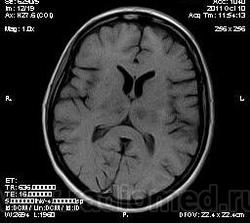

MELAS? Чем черт не шутит?

MELAS- по лаколизации очень похоже, но пока нет достоверных данных на него указывающих

Тогда КТ надо еще сделать, для исключения кальцинатов в базальных ганглиях.

Я неприклонен... Инфаркт ЗМА (вероятно, варианта развития левой ЗМА - эмболии, мойа-мойа..).

За MELAS, с учетом его патогенеза, не вижу серьезных аргументов.